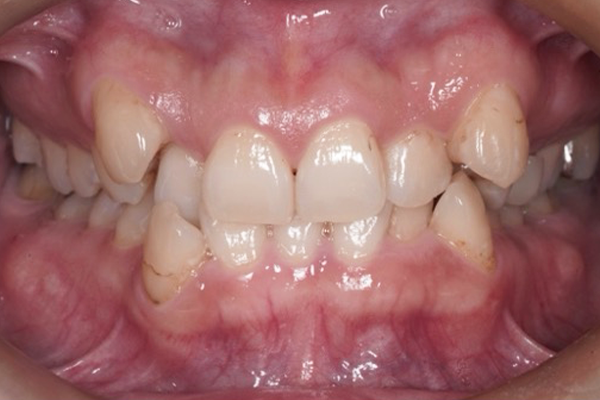

1.口腔内写真・顔貌写真の撮影

お口の中の写真と、正面・横顔の写真を撮影します。

これは単なる記録ではなく、歯並びと顔全体のバランスを分析するために欠かせない資料です。

治療前後の比較にも活用でき、患者さま自身が変化を実感しやすくなるメリットもあります。